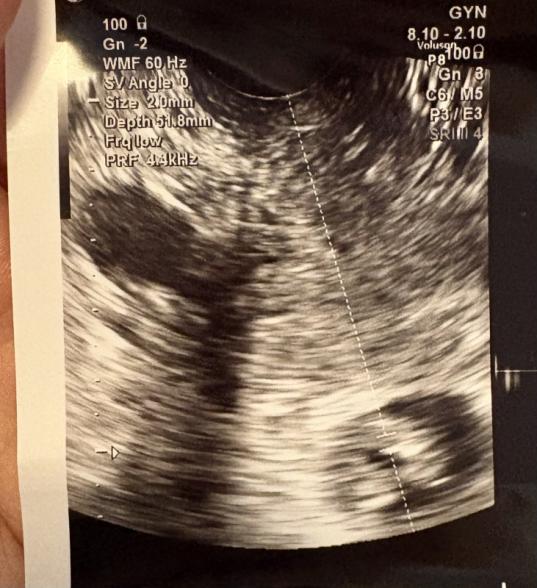

病院受診しまして、本日が8w1dでお話をもらいました。

心臓が動いているのも確認出ましたが、

先生が小さいなーと言っていたのが気になります。

私自身胎芽(胎児)の大きさに比べて胎嚢小さいなと思ったので、心配です。

胎児の大きさに対して胎嚢が小さいのは許容範囲なのでしょうか。。

胎嚢の正確な大きさが分からないので、お写真からだけでは何とも判断しにくいですが、ご妊娠初期はまだ不安定な時期ですし、例えば月経周期がバラバラだったりすれば、週数がずれている可能性が高いのではないかと推測します。予測の週数よりも胎嚢が小さかったとしても、その後お子さんの発育がしっかりとみられているのであれば、単なる週数のずれで、あまり問題ないですので、今は赤ちゃんの生きる力を信じて、見守ってあげてくださいね。

エコー検査をしてみて「少し胎嚢が小さいですね」と医師から言われると、ご心配になるママさんも多いのですが、そのあと心拍などがしっかり確認できていて、赤ちゃんなりに発育がみられるのであれば、赤ちゃんが順調に発育している証拠ですよ。